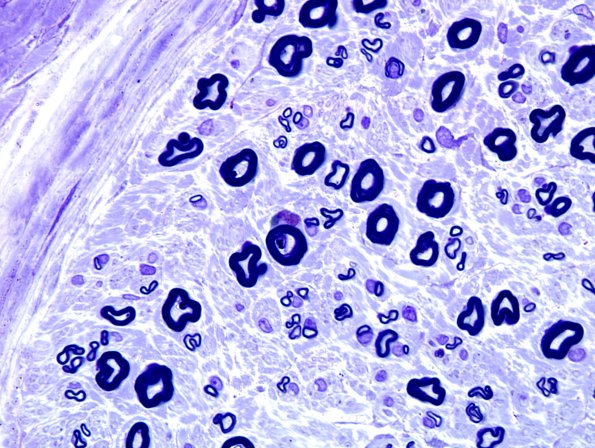

Washington University Experience | PERIPHERAL NEUROPATHY | 4 AXONAL DEGENERATION | 2 Plastic Sections | 20A3 Fiber loss, small exaggerated (Case 20) Plastic 9 (best)

There is moderate loss of large myelinated axons with a significantly decreased population of small myelinated axons which are present mostly as regenerative clusters